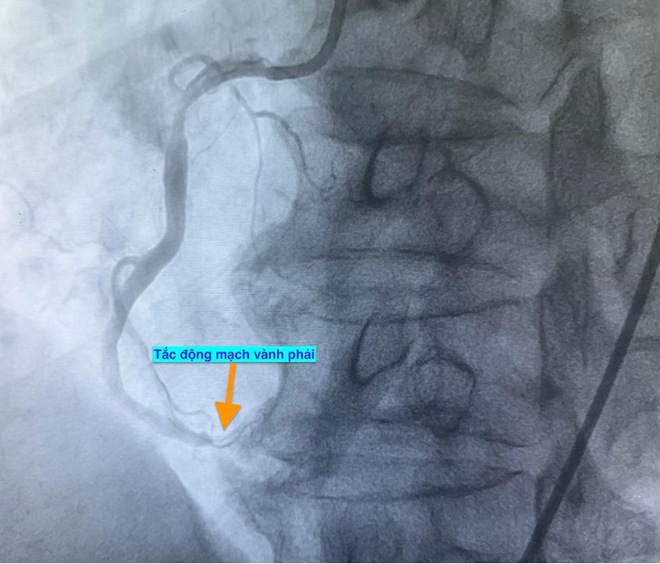

Trường hợp thứ nhất, lúc 0 giờ 34 phút ngày 14.11, nam bệnh nhân 51 tuổi vào bệnh viện vì mệt và khó thở. Chụp mạch vành phát hiện bệnh nhân bị tắc hoàn toàn động mạch vành phải.

Trường hợp thứ hai, lúc 9 giờ 5 phút, nam bệnh nhân 53 tuổi nhập viện vì chóng mặt và nóng rát thượng vị. Điện tâm đồ ghi nhận nhồi máu cơ tim cấp vùng dưới. Kết quả chụp mạch vành xác định bệnh nhân cũng bị tắc động mạch vành phải.

Hình ảnh chụp mạch vành cho thấy các bệnh nhân bị tắc mạch máu tim (do mảng xơ vữa, huyết khối) dẫn đến tình trạng thiếu máu cục bộ và nhồi máu cơ tim cấp